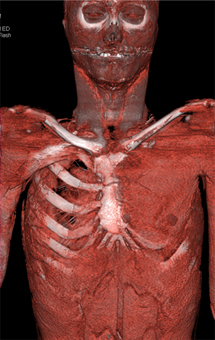

On this follow-up study for a vascular ring we also define

Polands syndrome

Loeys Dietz syndrome

Rasmussens Triad

Marfans syndrome